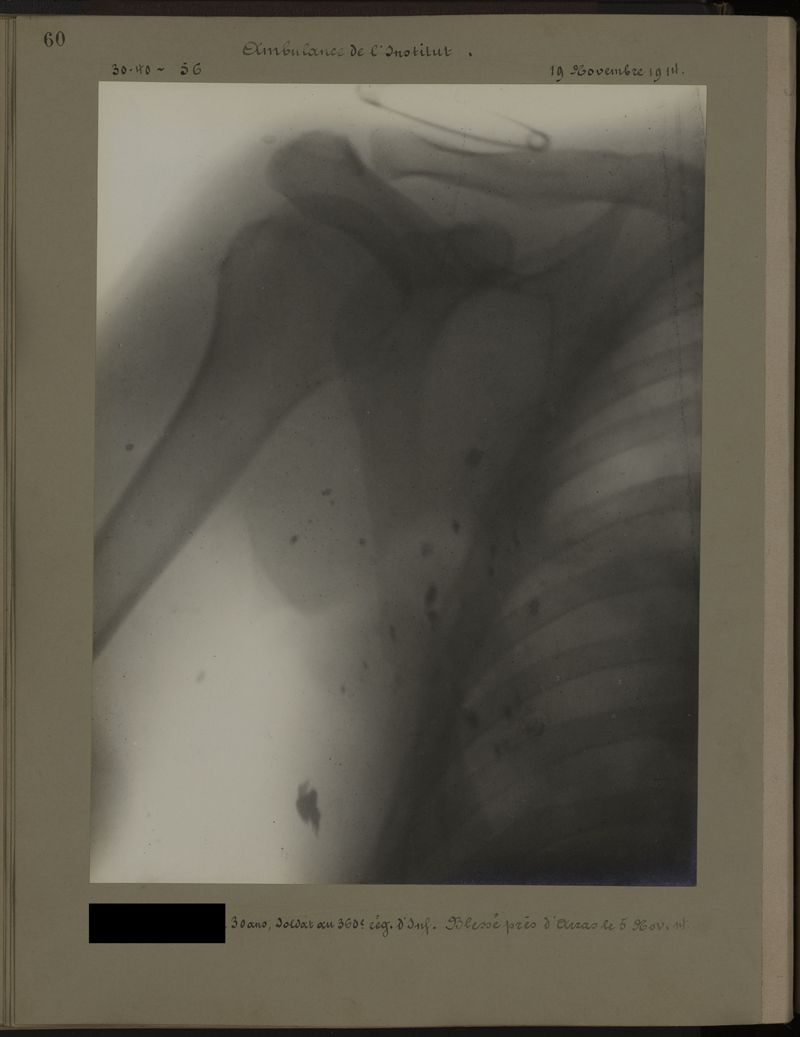

Deux albums de radiographies de la Première Guerre mondiale. Collection du laboratoire central de radiographie de la Salpêtrière. Deuxième album.

1915.